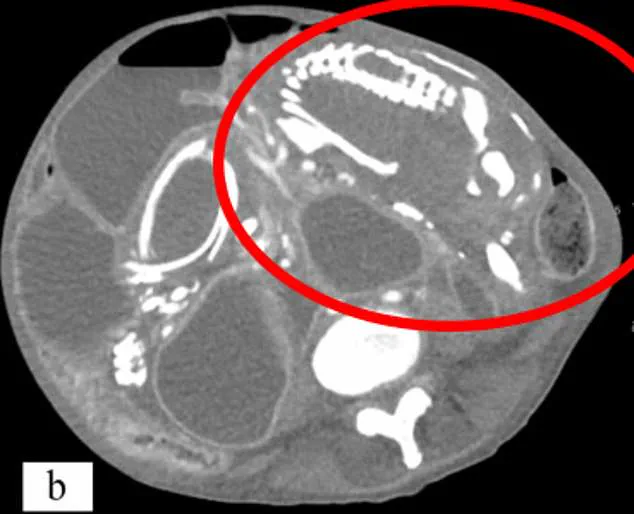

Medical experts emphasize that the body's response to a nonviable pregnancy is both complex and protective. When the fetus dies, the immune system recognizes it as a foreign object, triggering a process that encases the remains in calcium to prevent infection. This mummification can lead to a mass that causes chronic pain, digestive issues, or even life-threatening complications if left untreated. In 2023, a 50-year-old woman in New York experienced severe malnutrition after a lithopedion compressed her intestines for nine years. Her condition went undiagnosed until scans revealed the calcified fetus, which she had mistakenly attributed to a spiritual curse.

Another tragic example involves an 81-year-old woman in Brazil who died after surgery to remove a lithopedion she had carried for over 56 years. Doctors discovered the calcified mass during a routine scan for stomach pain, revealing a fetus from a pregnancy more than half a century prior. These cases underscore the importance of early detection through modern prenatal imaging and blood tests. Today, healthcare professionals use detailed ultrasounds and hormone monitoring to identify pregnancies of unknown location (PUL), ensuring timely treatment with medication or surgery.